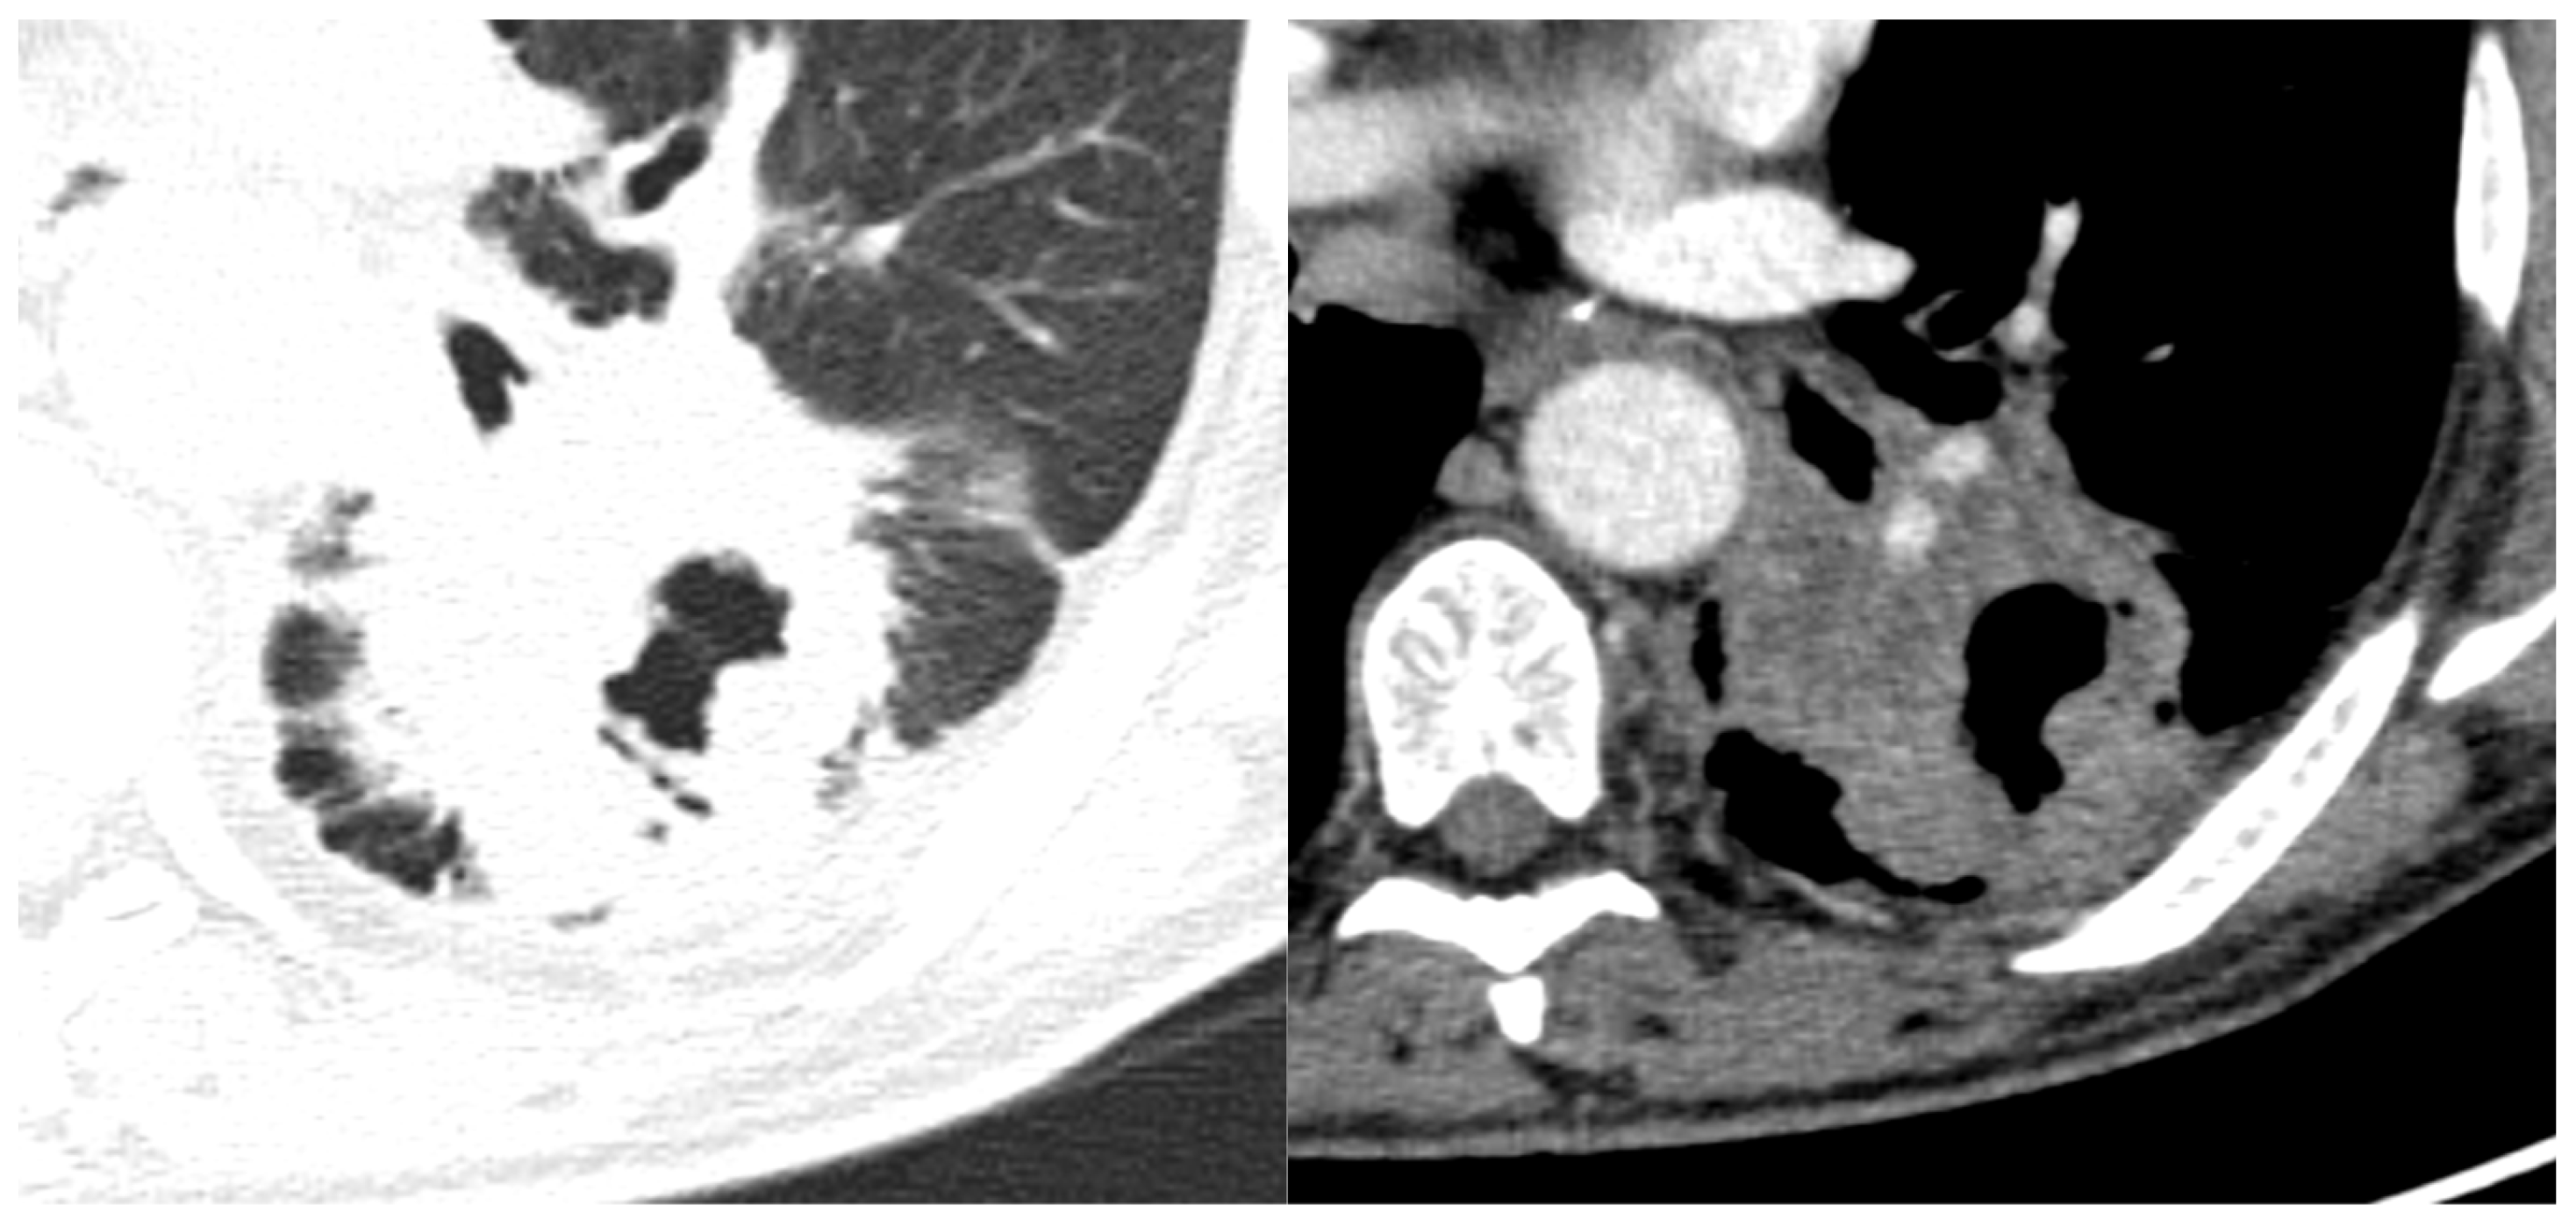

3.2.4. Cavitation

3.2.5. Local Invasion

3.2.6. Other Features—Bronchial Obstruction and Vascular Bundle Thickening